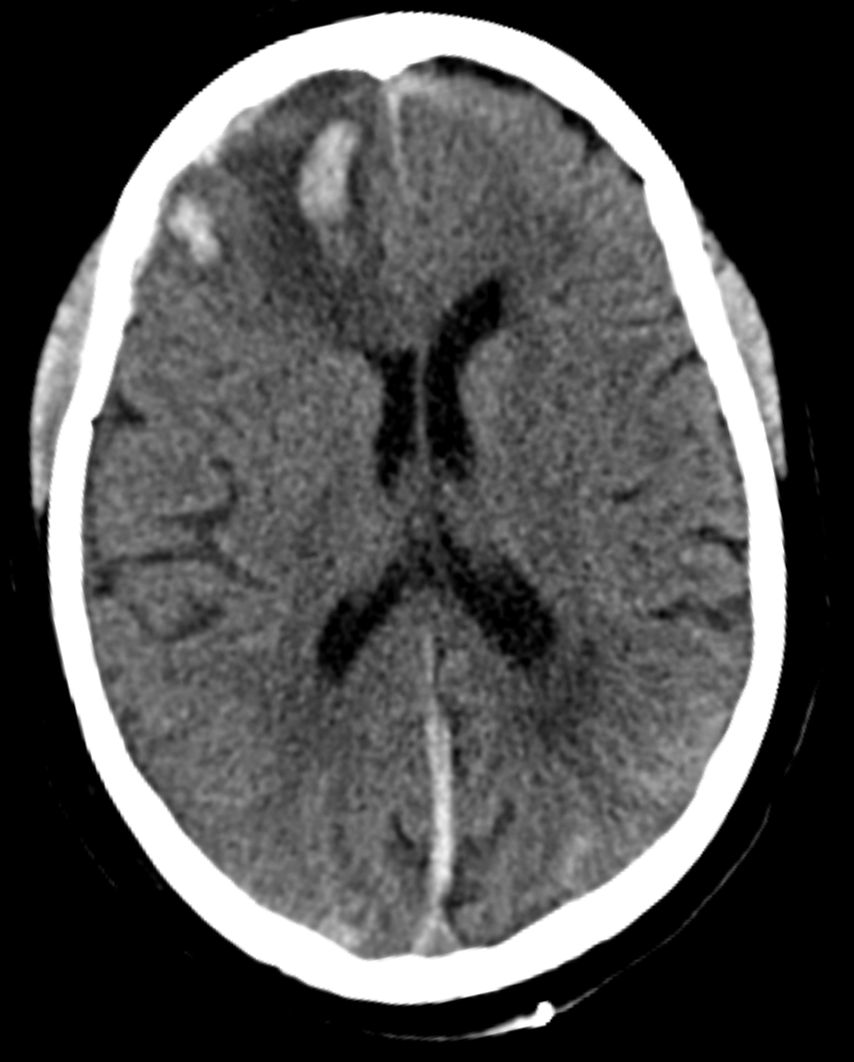

CT-scan of a frontal intracerebral hemorrhage on the right (left image side) as a contre coup. There is dens suture material visible left occipital in the skin.

Brain trauma CT. - Primary brain injuries, Secondary brain injuries